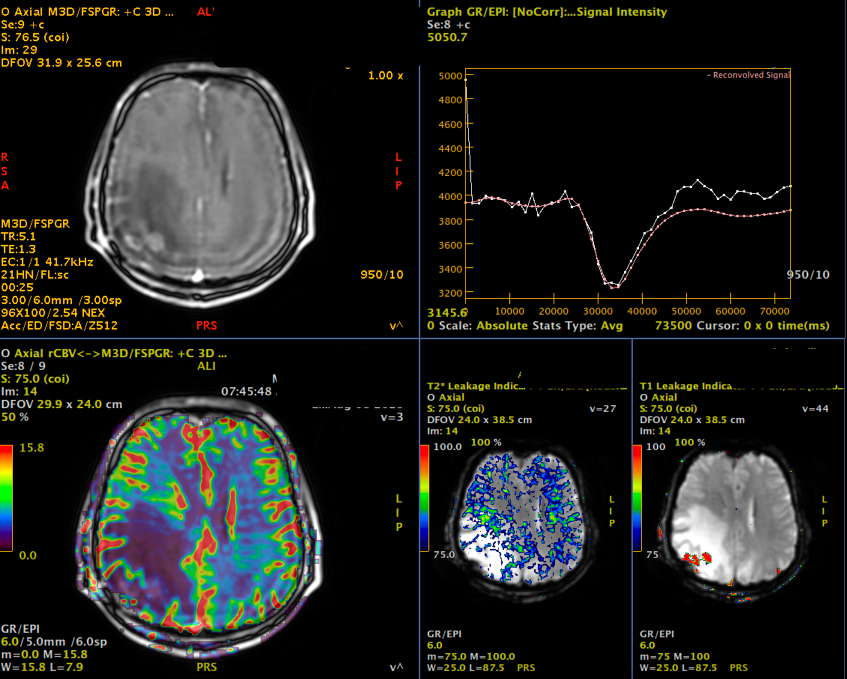

Pe lângă secvențele convenționale, tehnicile avansate aduc informații suplimentare:

- perfuzia evidențiază angiogeneza tumorală

- spectroscopia reflectă metabolismul celular

- DTI (tractografia) arată relația cu tracturile din substanța albă

Cu toate acestea, niciuna dintre aceste metode nu poate delimita complet infiltrarea microscopică. De aceea, planificarea chirurgicală și terapeutică trebuie să țină cont de această limitare.